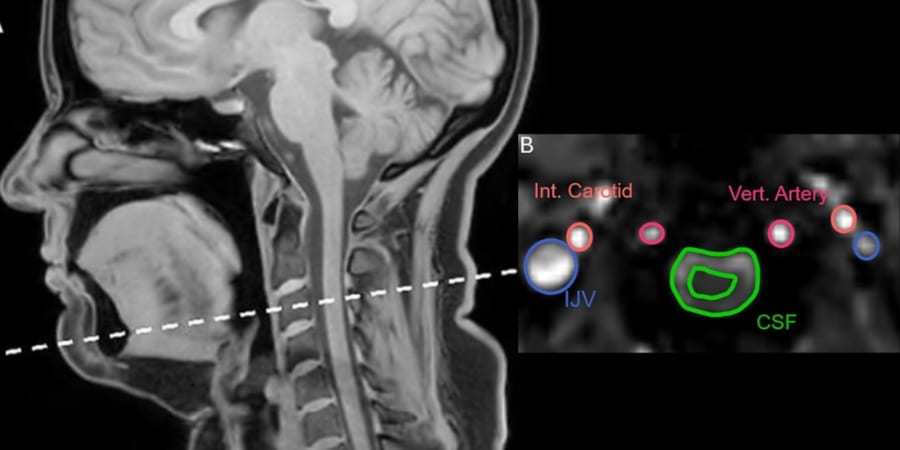

そのあいだに首の上の方、首の骨でいうと三番目あたりで、脳脊髄液の流れと内頸静脈を流れる血液の流れが、どの向きにどれくらいの速さで動くのかを、別々に連続的に記録しました。